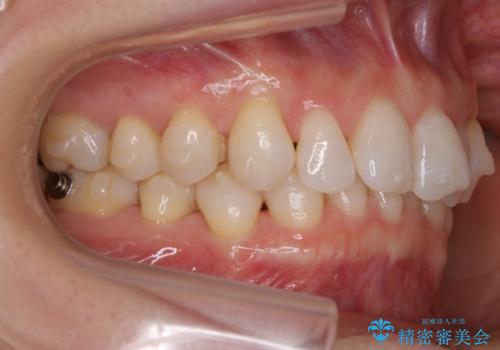

【抜歯】矯正治療とインプラントで正常な噛み合わせを実現

- 元々は矯正治療を主訴にご来院されました。

治療を始めるにあたり、精密検査を受けていただき全体の状況を把握したうえで矯正治療の計画を立てることとなりました。

その過程で左下の6番目の歯は治療が必要な状態であることが分かり、被せ物を外して内部を確認してみると根が破折してしまっていることが判明しました。

歯が深い位置で破折している場合は基本的には抜歯が選択されます。

様々な治療プランを患者さんと相談させて頂き、最終的にインプラントで噛み合わせを回復させていくこととなり、まず悪くなっている歯を抜歯することから開始しました。